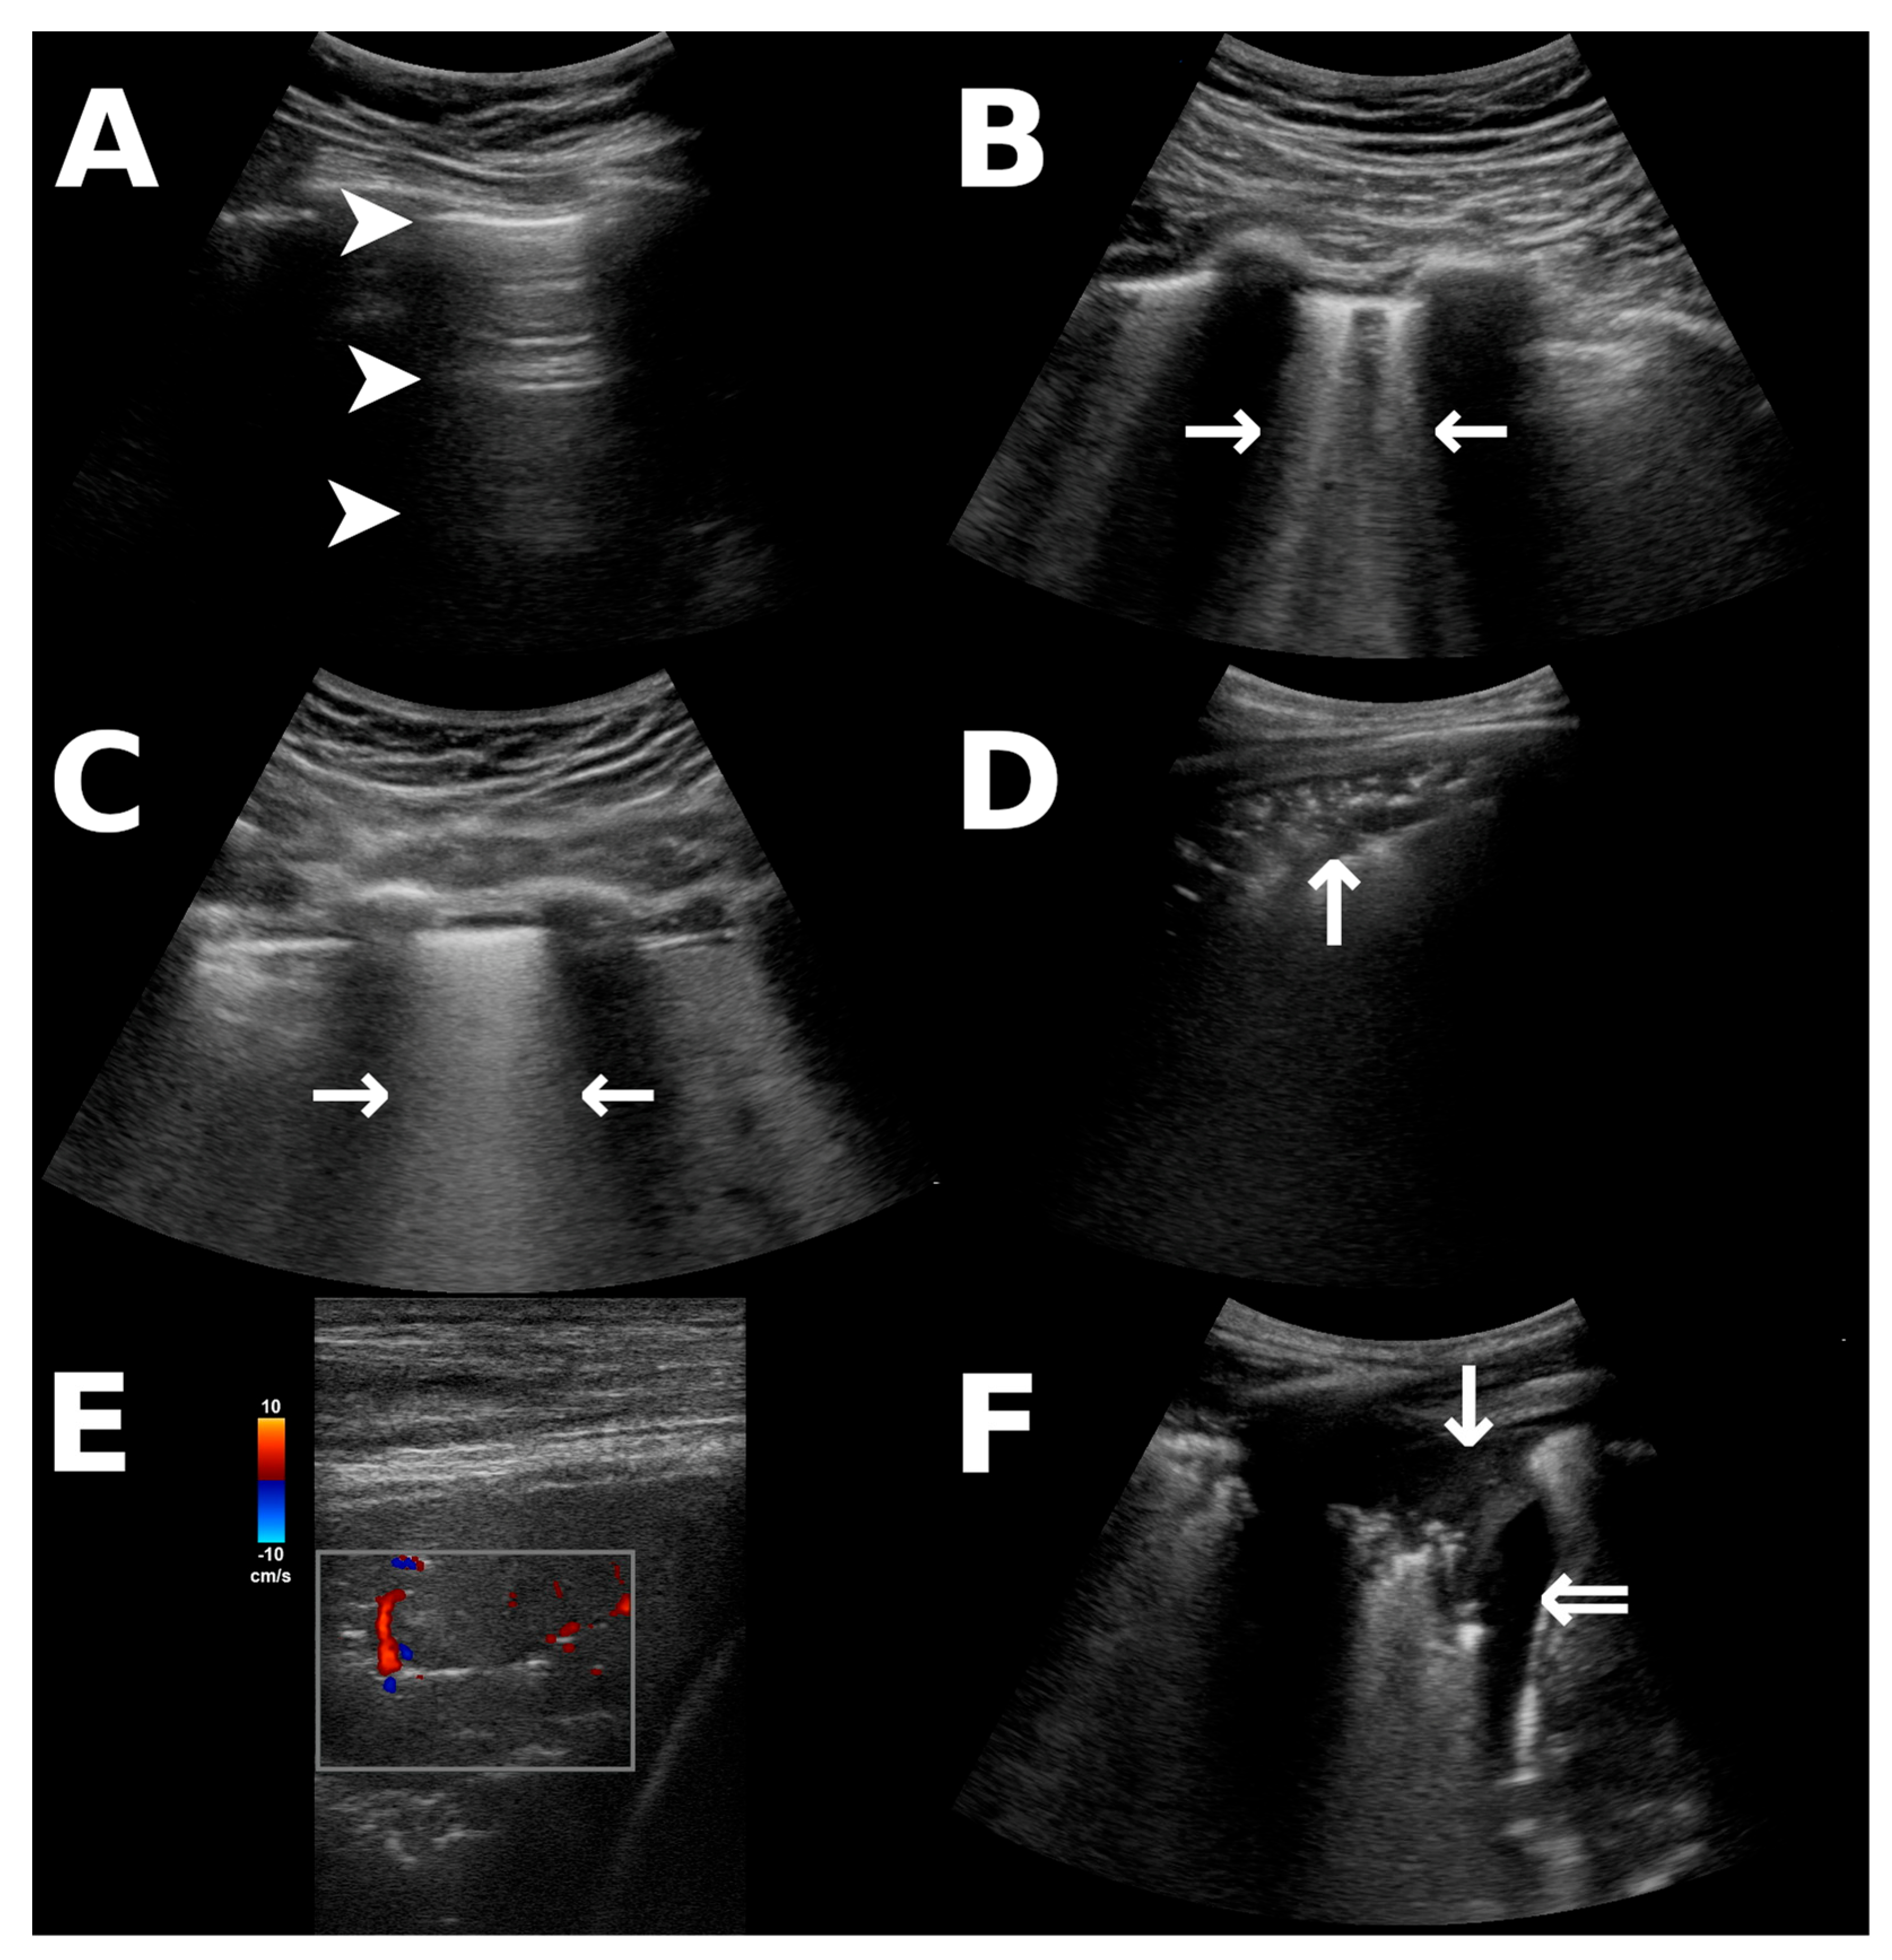

During the ongoing pandemic of coronavirus disease-19 (COVID-19), lung ultrasound (LUS) has emerged as a powerful diagnostic tool in detecting the pulmonary involvement of infection [1]. LUS provides bedside imaging without radiation exposure and can be repeated perpetually while providing a higher sensitivity than bedside radiography, particularly in COVID-19 [1,2]. Interstitial involvement in lung disease is indicated by B-lines on LUS [3,4], which are distinguishable in moderate pathologies (Figure 1B) and may form indistinguishable, coalescent B-lines (Figure 1C) when interstitial involvement progresses to alveolar edema, corresponding to “white lung” in conventional imaging [4]. B-lines may occur in infectious disease, pulmonary edema, and other interstitial lung diseases [3,4]. Furthermore, consolidations that reach the pleura and pleural effusion (Figure 1D–F) are detectable via LUS [1,3]. Critically ill patients are at a high risk of suffering from complications during in-hospital transport to acquire radiological imaging [5], whereas LUS can be performed at the patients’ bedside. Many pulmonary complications in the intensive care unit (ICU) unrelated to COVID-19, for instance, the development of a pneumothorax, are also reliably detected via LUS [4].

Figure 1.

Ultrasonographic findings that were incorporated into the scoring system. All images were obtained from patients in our study population. (A) A-lines as reverberations of the pleural line (arrowheads) indicate fully aerated lungs or pneumothorax, distinguishable by dynamic pleural gliding [3,4]. (B,C) B-lines (horizontal arrows) arising from the pleural line indicate interstitial pathology and appear distinct (B) or merge to form coalescent B-lines (C), the latter corresponding to alveolar edema [4]. (D) Peripheral consolidations (vertical arrow) appear tissue-like and may contain hyperechoic air bronchograms. (E) Color Doppler ultrasonography of a pulmonary consolidation (red: flow towards the ultrasound probe, blue: flow away from the probe; scale for reference) in COVID-19 may demonstrate diminished pulmonary perfusion [1]. (F) Atelectatic lung (vertical arrow) within a pleural effusion (double arrow).

The score shows a moderate correlation with oxygenation impairment as indicated by the oxygenation (or Horovitz) index (Figure 4a). LUS primarily assesses ventilation as well as interstitial pathologies. However, COVID-19 also disrupts lung perfusion by promoting thromboembolic events and right-to-left-shunting by impairing hypoxic vasoconstriction [15,16]. Sonographic assessment of pulmonary perfusion is limited, as it can only be evaluated peripherally when consolidations are present [1,17]. Although the pulmonary perfusion deficit appears to be qualitatively representable on color Doppler ultrasonography of consolidations (see Figure 1E) [1], no quantitative sonographic measurements or diagnostic criteria are available at this point. Furthermore, not all patients with impaired pulmonary perfusion will present with conveniently located consolidations that can be utilized as ultrasound windows. LUS may, therefore, not depict all aspects of the pathophysiology of COVID-19, resulting in the broad range of the observed oxygenation indices. Differently sized consolidations will also yield the same scoring, although the limitation of the regional ventilation might be different for small subpleural or large segmental and lobar consolidations. However, implementing an overly complicated score that would appreciate all facets and configurations of possibly encountered image artifacts would be impractical for clinical use. The score is, mathematically speaking, an ordinal variable; the arbitrary intervals do not reflect identical increments in respiratory impairment. We attempted to address this by using an appropriate polyserial correlation model that accounts for correlation analysis between ordinal and continuous variables [18]. The change in score furthermore correlates to changes in oxygenation between examinations (Figure 4b). Decreasing scores might indicate a resolving pathology, as suggested by the stronger correlation between negative changes in score and corresponding improvement in oxygenation. Similarly, a study in patients receiving ECMO therapy prior to the COVID-19 pandemic found that survivors’ LUS scores decreased over the course of treatment, as opposed to non-survivors’ scores [8]. LUS could, therefore, be utilized to monitor pulmonary involvement over time, particularly due to its availability in the ICU and lack of irradiation.